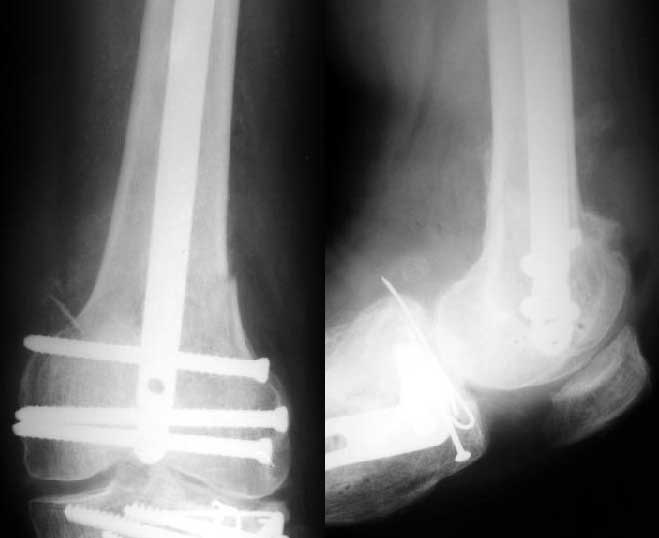

Мужчина 52 лет оперирован у нас 1,5 года назад по поводу перелома проксимального отдела большеберцовой кости. Все было неплохо, сгибал колено градусов до 60, ходил с полной нагрузкой, давно уже работал (служащий). Пару дней назад упал на скользкой улице - снимок в приложении. Какие предложения по лечению (пока первая мысль опять про закрытый интрамедуллярный остеосинтез)? И более широкий вопрос - как быть с локальным остеопорозом от бездействия после травм?

Merry Xmas!!! A male 52 years old was treated 1,5 years ago in our unit - ORIF of the proximal tibia. In 1 year follow-up all was OK - flexion 130, full WB, returned to work (white collar). Two days ago he fell on a slippery sidewalk - x-rays attached. How would you manage the injury? My first thought is closed nailing. And more common question - what we should do routinely with posttraumatic local osteoporosis? When full WB and function of the extremity is restored how long does a problem of such fractures exist?